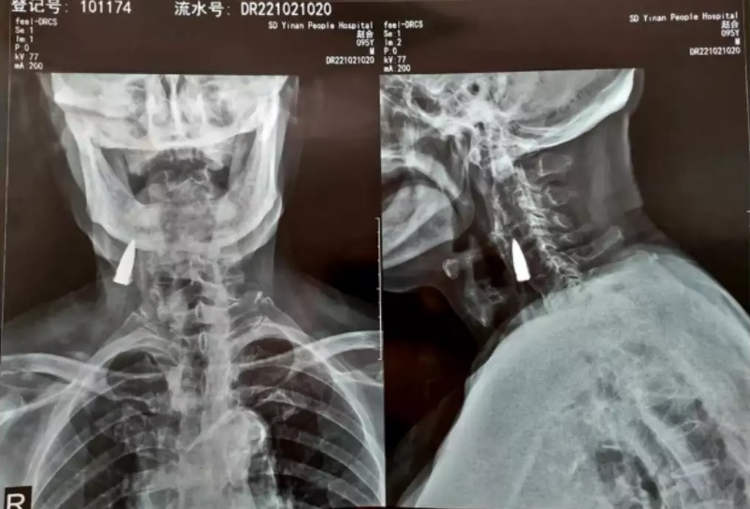

Αφού άκουσαν για την πτώση του, οι γιατροί του συνέστησαν μια ακτινογραφία, για να βεβαιωθούν ότι δεν είχε υποστεί σοβαρή βλάβη στον αυχένα του. Μόνο που αντί για κάταγμα, η ακτινογραφία αποκάλυψε ένα ξένο αντικείμενο στο λαιμό του άνδρα, το οποίο αργότερα θα αναγνωριζόταν ως μια παλιά σφαίρα.

Ο ίδιος ο Ζάο εκτιμά ότι η σφαίρα βρισκόταν στο λαιμό του από το 1944, όταν χτυπήθηκε από σφαίρα ενώ διέσχιζε ένα ποτάμι. Η σφαίρα φέρεται να μπήκε μέσα από την αριστερή πλευρά της μύτης, διαπέρασε την άνω γνάθο του και του έβγαλε ένα από τα δόντια του πριν σφηνωθεί στον λαιμό του. Ωστόσο, αυτό είναι μόνο το προαίσθημά του.

Αφού εξέτασαν τις ακτινογραφίες, οι γιατροί είπαν στον Zhao He και την οικογένειά του ότι η σφαίρα ήταν κοντά σε κάποια σημαντικά αιμοφόρα αγγεία και ότι, εφόσον δεν του είχε προκαλέσει κανένα πρόβλημα, ήταν καλύτερο να την αφήσουν μέσα. Ο βετεράνος πολέμου συμφώνησε.